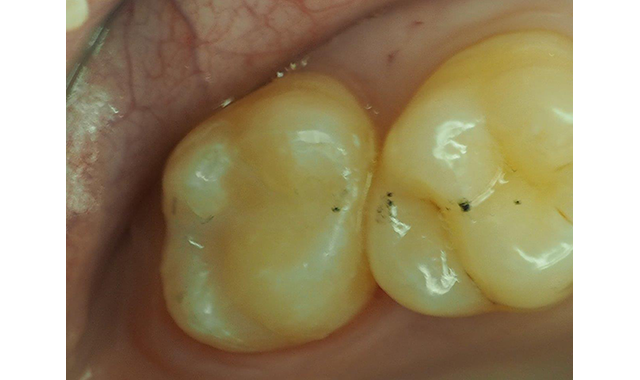

The rubber dam was then removed, and the occlusion adjusted with a spiral multi-fluted carbide bur followed by fine polishing with Rally points from Garrison Dental Solutions (Fig. 10).

Fig. 10 The occlusion was adjusted and the final polish accomplished with spiral multi-flute carbide bur and polishing points.

The patient’s parents were contacted the next day to check on the postoperative sensitivity and they were pleased to report the patient had none. In this situation, the desensitization of the prepared dentin delivered an exceptional restoration outcome, without post-op sensitivity and improved the dental attitude of this young dental patient.